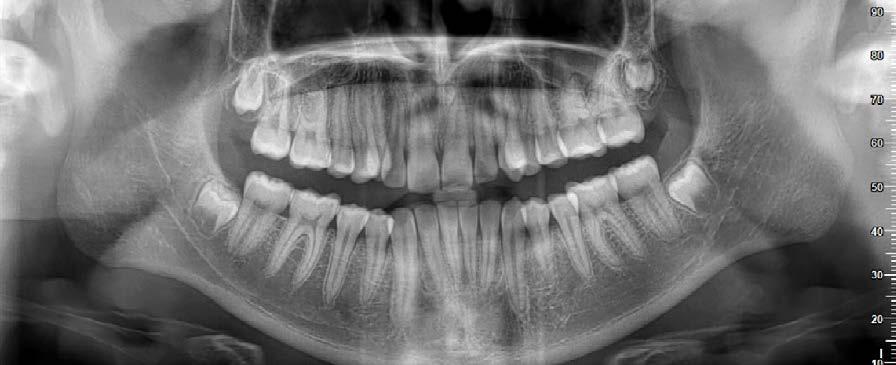

Figura 7. Lefort I. Figura 8. Osteotomía sagital. Figura 9. Mentoplastía. Figura 10. Cefálica de progreso. Figura 11. Panorámica de inicio.

Fueron realizados después de 1 año y 2 meses de haber iniciado el tratamiento y después de la cirugía. En los estudios radiológicos tenemos que en la radiografía lateral de cráneo las placas utilizadas para consolidar la fijación de los maxilares, la corrección de las relaciones esqueléticas en la Figura 10. En la panorámica inicial se señalan los gérmenes de los terceros molares (Figura 11) y en la Figura 12, la realización de las exodoncias de órganos dentarios 18, 28, 38 y 48.